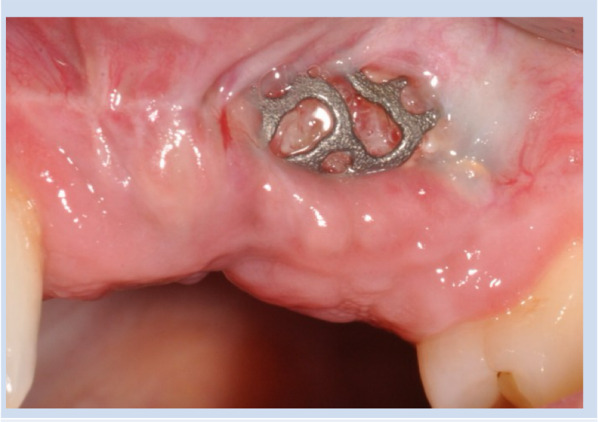

Purpose: This retrospective study aimed to evaluate the incidence of dehiscence following bone augmentation with patient-specific titanium meshes and to identify factors associated with its occurrence.

Material and methods: Patients who underwent bone grafting with patient-specific titanium mesh between December 2014 and October 2021 were included. The primary outcome was the occurrence of dehiscence. The occurrence of dehiscences was recorded during the following time phases, enabling the determination of whether dehiscences occur early (< 2 weeks), in the mid-term (2-9 weeks), or later in the healing phase (> 9 weeks).

Results: A total of 78 patients undergoing 85 titanium mesh augmentations were included, with a mean follow-up period of 1.2 years. Dehiscence occurred in 33 meshes (38.8%), with 51.5% of these events arising during the early healing phase. In no case was premature removal of the titanium mesh required due to dehiscence. A statistically significant association was observed between dehiscence and both smoking behavior (p < 0.001) and the anatomical location of the maxillary defect (p = 0.029). No significant associations were found between dehiscence and gender (p = 0.160), periodontitis (p = 0.512), gingival phenotype (p = 0.495), defect type (p = 0.490), augmented bone volume (p = 0.373), or incision type (p = 0.354). Logistic regression analysis further identified smoking (odds ratio: 7.07; 95% CI: 2.19-22.80) and maxillary defect alveolar (odds ratio: 11.86; 95% CI: 0.34-4.60) as significant predictors of dehiscence.

Conclusion: Dehiscence following customized titanium mesh augmentation was significantly associated with smoking and the location of the maxillary defect, underscoring the importance of early detection and timely intervention.